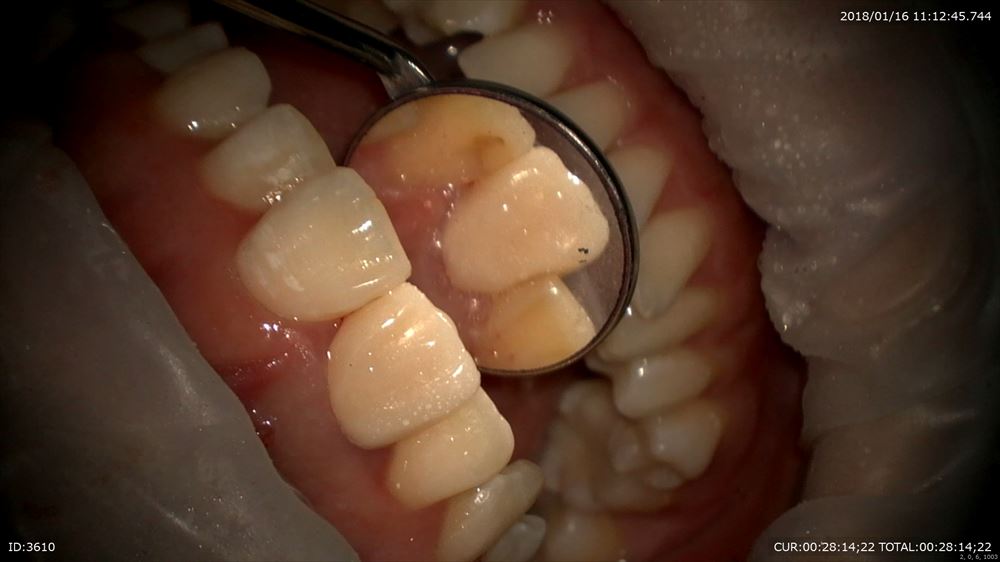

中はこんなに汚れています。

ここから精密な仮歯をオーダーメイドで作成。既成冠なんてだめです。

なるべく質感も同じにして前方のガイドもしっかりつけないといけないから。オーダーメイドの仮歯。

裏側もチエック。フィットOK。

これで準備完了。次回から精密根管治療スタート!